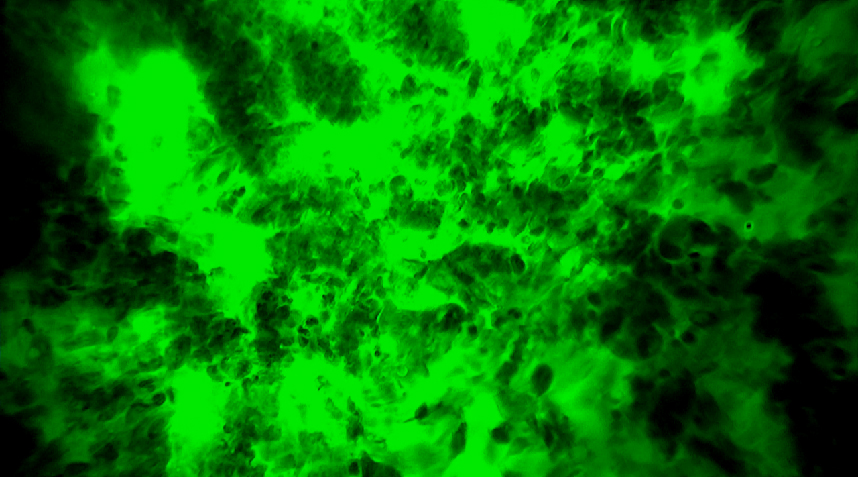

傳統(tǒng)手術(shù)路徑